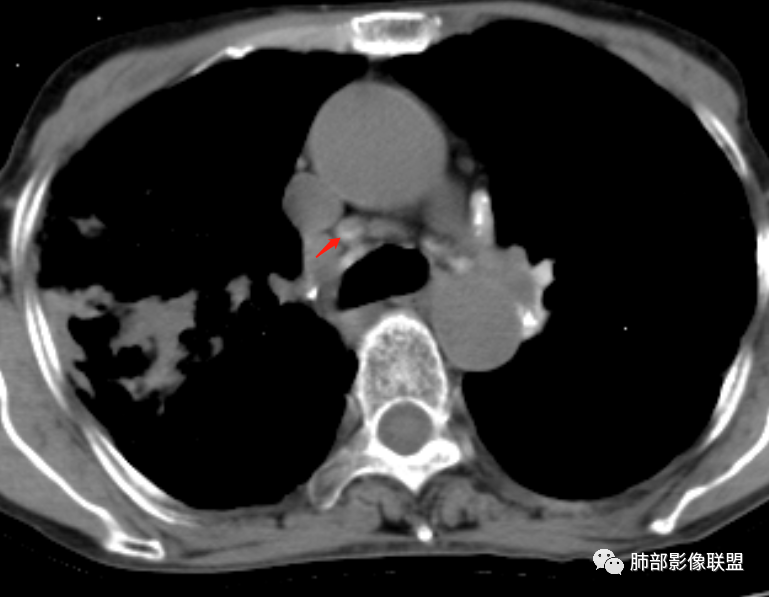

双肺多发斑片,索条及结节影,内可见钙化,右肺上叶后段支气管截断,断端圆钝略扩张,双肺门及纵膈淋巴结钙化,双侧胸膜增厚伴钙化。首先考虑结核。右肺上叶亚段气管分叉处结节,警惕肿瘤

老年女性,双肺索条纤维影,右肺上叶散在卫星灶,树芽征,小叶中心融合,右肺后段支气管圆形截断,实变病灶内支气管扩张,考虑结核。

就这里不让人放心,是占位吗?支气管是截断的,没有凹陷或者突出阻断,阻断前稍扩张

患者老年女性,亚急性起病,主要症状表现为咳嗽、咳痰半月余,查体:双现呼吸音粗,双肺可闻及痰鸣音。胸部CT:双上肺胸膜下可见多发小叶实变影,双上肺可见多发小叶中心性结节及小叶间隔增厚,右上肺后段可见亚段性实变影,内见多发空洞,前段可见GGO及树芽征,后段局部支气管闭塞,肺门淋巴结肿大并钙化。病灶整体:有气道、间质播散,一元论考虑肺结核合并支气管结核可能性大,建议好好查痰;这样病灶:明显实变+空洞+气道播散,若是结核,痰涂片找到抗酸杆菌应该没问题。建议支气管镜检查助诊,了解有无支气管结核及合并腺癌的可能。

1.双肺片状影、大小不等斑片影、结节影、树芽等,病灶密度偏高多钙化。

2.病灶上肺为主,胸膜下分布为主。双肺病灶明显不对称,右肺块状影较大。

3.纤维条索影广泛杂乱、牵拉,横向分布为主,这点给人也印象很深!

4.纵隔轻度右移。双肺门纵隔淋巴结增大钙化。